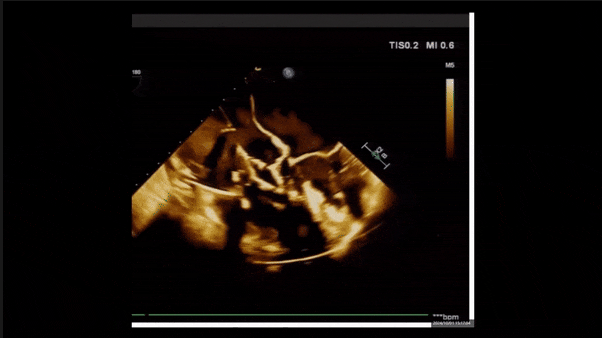

術(shù)后即刻返流三維

術(shù)后三維超聲

術(shù)后即刻經(jīng)食道超聲可見,三尖瓣假體瓣膜位置合適,牛心包瓣葉運(yùn)動狀態(tài)良好,開閉正常,瓣周及瓣葉對合緣處未見明顯返流,心電圖及心包狀態(tài)較術(shù)前無明顯變化。

術(shù)前術(shù)后返流情況對比